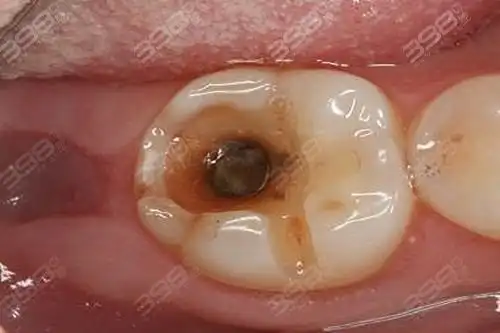

看蛀牙烂到牙神经图片了解牙齿烂洞长期不补会怎样